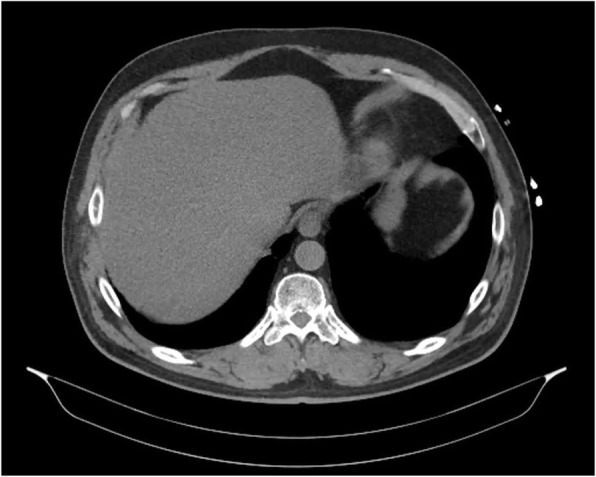

Over the next 24 hours, the patient continued to have intermittent high fevers. Empirical antibiotics were commenced (intravenous piperacillin/tazobactam 4.5 g three times daily). Blood cultures subsequently grew C. perfringens and E. avium; both organisms were sensitive to penicillin. Computed tomography (CT) of the abdomen and pelvis demonstrated cholelithiasis but was otherwise normal (Fig. Fig. 1). Specialist infectious disease advice was sought on two occasions, which confirmed appropriate antibiotic management. The patient continued to remain clinically stable.

Fig. 1.

Computed tomography (CT) of the abdomen and pelvis in a patient with suspected gastroenteritis. Image was obtained within 24 hours of presentation to the hospital. CT demonstrated cholelithiasis but no other abnormality